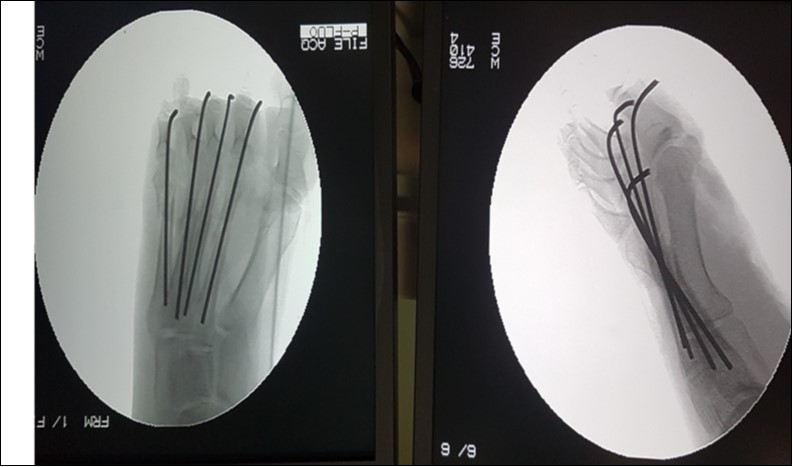

The open foot injuries in this study were treated by initial wound debridement followed by other procedures depending on the nature of the injury. Lacerations were debrided and sutured; where tendons were severed they were repaired as necessary, using standard repair methods. Open fractures were, after debridement, stabilized with K-Wires and thereafter, reinforced with a Plaster-of-Paris slab. Where skin defects could not be sutured, wound coverage was achieved by split skin grafting. None of the 81 patients studied required flap cover for a soft tissue defect. (Figure 1, Figure 2).

Figure 2.Check x-rays, anteroposterior and lateral views of the open right metatarsal fracture in figure 1, showing stabilization with 2.0-mm kirchner wires.